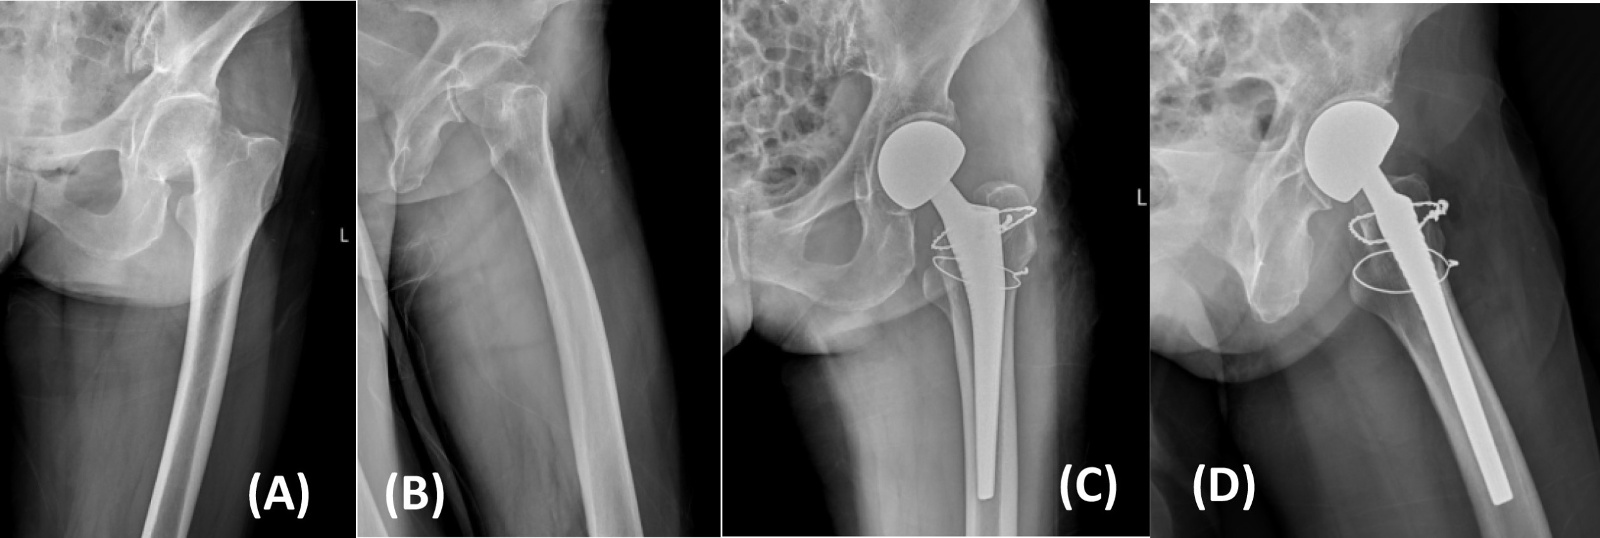

典型病例影像学表现见图1~5图1为70岁女性右侧股骨颈骨折(Garden Ⅲ型)患者,改良hardinge入路半髋关节置换术前X线示骨折断端部分错位,术后X线示假体位置良好;图2为85岁女性左侧股骨颈骨折(Garden Ⅲ型)患者,术后X线示假体位置良好;图3为83岁男性右侧股骨颈骨折(Garden Ⅲ型)患者,术后假体位置满意;图4为91岁男性左侧股骨颈骨折(Garden Ⅳ型)患者,术后假体匹配良好;图5为75岁女性左侧股骨颈骨折(Garden Ⅲ型)患者,术后假体位置正常,股骨近端微裂予钢丝捆扎固定。

Figure 1. X-rays before and after modified hardinge approach hemiarthroplasty in a 70-year-old female patient with right femoral neck fracture (Garden type III) (A), (B). Before operation; (C), (D). After operation

1. 70岁女性右侧股骨颈骨折(Garden III型)患者改良hardinge入路半髋关节置换手术前后X线片(A)、(B) 术前;(C)、(D) 术后